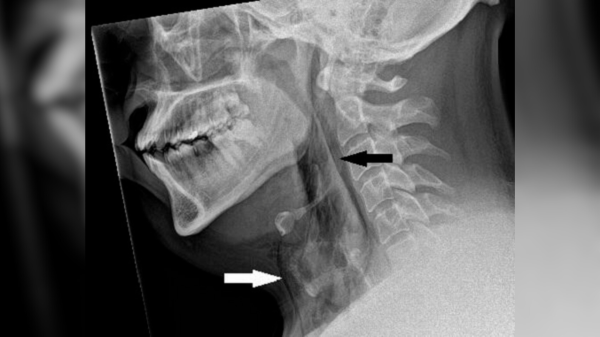

Чоловік стримав чхання — і воно пробило йому трахею